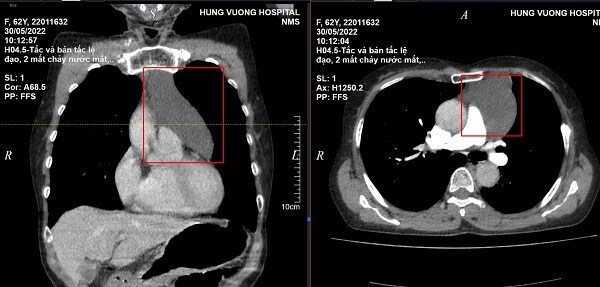

Kết quả chụp X-quang cho thấy trong cổ họng bệnh nhân có một con cá rô phi dài khoảng 12.7 cm, sống lưng, đuôi và vây đều được bao phủ bởi những chiếc gai nhọn. Con cá mắc kẹt giữa cổ họng và khoang mũi của người đàn ông.